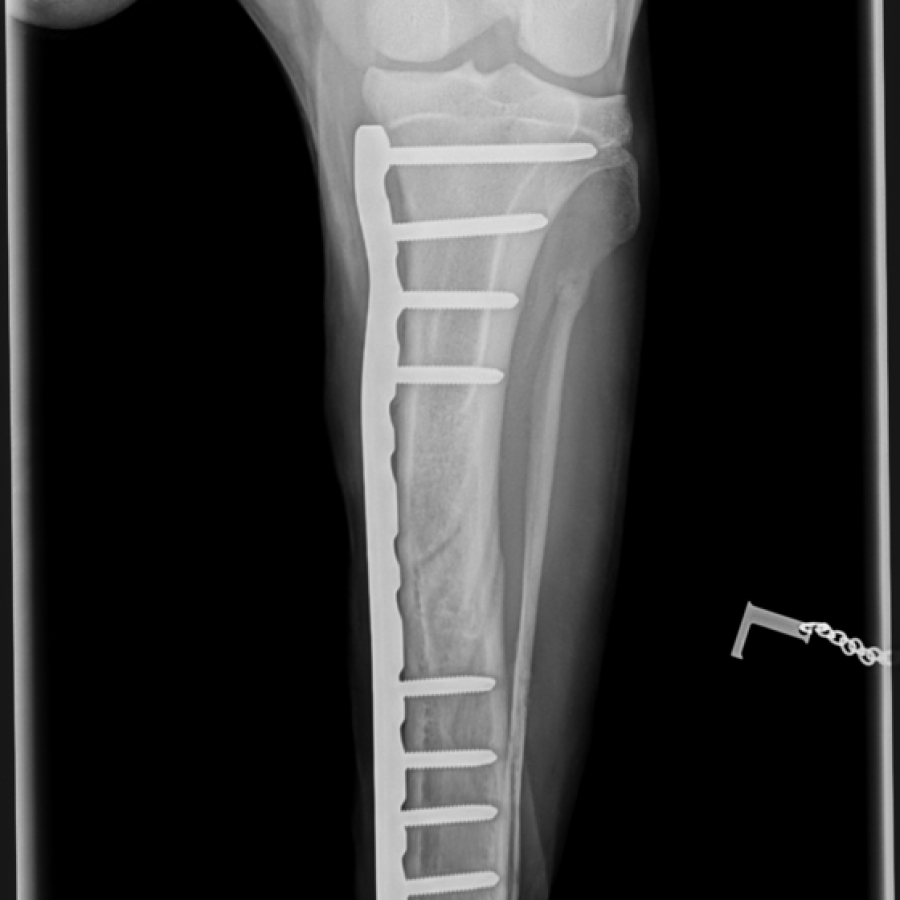

Am 07.08.2023 ist es passiert. Das Unglück – Josh hat sich bei einer für ihn ganz normalen Bewegung eine Fraktur der Tibia und Fibula im linken Bein zugezogen. Nun hieß es erstmal erste Hilfe leisten. Ich konnte Josh beruhigen und sein Bein stabilisieren. Ich legte Josh zur Sicherheit eine Maulschleife an. Aber wie bekomme ich den Hund ins Auto? 37 Kilo wollen getragen werden. In der Zwischenzeit kündigte ich in der Tierklinik den Notfall an. Gott sei Dank war eine 2. Person anwesend. Ich versuchte ein Handtuch unter Josh zu schieben. Darauf konnte ich ihn die letzten Meter zum Auto ziehen. Mit einem beherzten schnellen Hochheben lag Josh im Kofferraum und dann ab zur Klinik. Dort angekommen war dann erst einmal Schmerzmanagement angesagt. Josh stand unter Schock. Josh musste in der Klinik bleiben. Am nächsten Tag hatte er sich soweit stabilisiert, dass er operiert werden konnte. Aufgrund der Größe des Hundes und dem Energielevel von Josh entschied man sich für eine Plattenosteosynthese. Die OP verlief nach Plan und Josh blieb zur Sicherheit noch eine weitere Nacht in der Klinik zur Beobachtung, da er etwas viel Blut gelassen hat.

Woche 1 bis 3 lief relativ unspektakulär. 3-4x täglich nur zum Geschäft erledigen raus, danach ging es wieder in den Käfig. 2x in der Woche ging es zum Verbandwechsel in die Klinik. Hier zeigte sich, wie wichtig ein „medical-training“ bereits im Welpenalter sein kann. Josh war ein vorbildlicher Patient und die Tierärzte konnten ihren Job erledigen. Zusätzlich bekommt Josh Schüssler Salze, CBD Öl und Chlorella mit ins Futter. Da Josh in einer hervorragenden körperlichen Verfassung ist, wird es zusehends schwerer ihn langsam gehen zu lassen. In Woche 3 machte die Haut nicht mehr mit und nachdem die Hautklammern entfernt wurden, musste auch der Verband ab. Das Bein ist noch etwas dicker als das andere, ist aber ganz normal 2,5 Wochen nach der OP. Die OP-Narbe sieht schon gut aus. Bisher keinerlei Entzündungen im Bereich der Narbe. Josh hat den Verband toleriert und konnte ohne Halskragen bleiben. Nun nachdem der Verband ab war, versuchte er natürlich wieder an den OP- Bereich dran zu kommen. Also kam der Halskragen wieder um. Die ersten physiotherapeutischen Behandlungen beschränken sich erst einmal auf die Gewebsaktivierung und Heilung der OP-Bereiches mit dem Amplivet 3.0, das Lösen der Verspannungen und passive Bewegungsübungen. Da eine Titanplatte verbaut wurde, ist die Behandlung mit dem Laser im OP-Bereich noch kontraindiziert. Dafür kommt der Akupunkturlaser zum Einsatz. Die Meridiane sind alle doppelt vorhanden und die wichtigen Punkte liegen alle weit genug weg.

Woche 6 - Das Nachröntgen

Die Spannung stieg als wir auf dem Weg in die Tierklinik waren. Wie wohl der Bruch nach 6 Wochen aussieht? Wir wurden freudig empfangen und Josh ging brav mit in den Röntgenraum. Dann endlich der Blick auf die Bilder. Ja der Knochen ist soweit gerade, keine Verschiebungen, aber alles noch nicht stabil genug für die Vollbelastung. Also weiterhin nur kurze Runden im Schritt für die nächsten 2 Wochen. Dann dürfen wir langsam die Streckenlänge weiter erhöhen. Der Muskelaufbau kann fortgesetzt werden. Das Bein darf im Stand und im Schritt etwas mehr belastet werden. Wir haben in 4 Wochen noch einmal einen Termin zum Röntgen. Ich fühle mich dadurch sicherer und möchte natürlich nichts verpassen wenn es Komplikationen gibt.

Röntgenbilder

direkt nach der OP und 6 Wochen später

Genau 10 Wochen post OP habe ich Josh noch einmal röntgen lassen. Das Bein sieht deutlich besser aus und wir dürfen wieder in die Normalität zurück.

Woche 14

12 Monate Post OP

Josh zeigte in den letzten Monaten immer wieder intermittierende Lahmheiten. Es war nicht wirklich klar, ob diese von der Fraktur oder der HD kamen. 12 Monate Post Op stand noch einmal ein Kontrollröntgen an. Die Fraktur war immer noch deutlich zu sehen. Lt. Klinik war alles in Ordung aber man müsse damit rechnen, dass die Platte abgestoßen wird und es zu Komplikationen kommen wird. Ich entschied mich zu einer Zweitmeinung und es wurde dringend empfohlen die Platte zur entfernen.

Die OP wurde durchgeführt und die Platte entfernt. Josh war nach 2 Wochen wieder auf den Beinen und bekam das Go für die Freiheit. Trotz der OP ist das Bein im distalen Bereich nicht wieder gerade gewachsen, es hält aber derzeit dem Druck stand und er läuft deutlich entspannter als vorher.